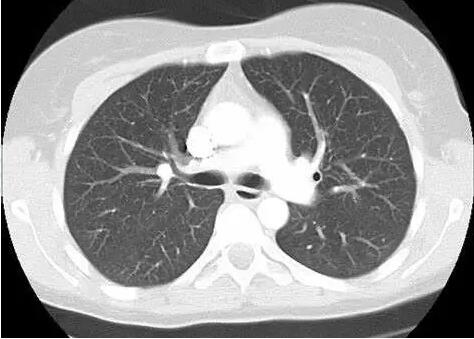

No.2 计算机体层摄影(CT)

CT是体层摄影,也就是说可以像切片将每一层组织进行摄影,因此显示比胸片清晰很多,在肺癌诊断筛查中有不可替代的地位,由于扫描层数多,因此辐射比胸片也高很多,常规CT检查的辐射量为胸片的60~100 倍,不宜作为肺癌的常规筛查方法。但是,低剂量螺旋CT的辐射量仅约为常规CT的1/4。美国国家肺癌筛查试验(NLST)证实:一年一次的低剂量螺旋CT筛查不会对筛查者的健康造成危害。

低剂量螺旋CT是最有效且安全的肺癌早期筛查手段,可以检出直径<1 cm的微小肺癌,其对早期肺癌的检出率高达80%。CT 筛查出来的早期肺癌患者中有80%~90%可以通过微创手术切除获得治愈,无须接受进一步放化疗。

对于筛查发现肺内有可疑小结节的人群,应结合其具体病情,进行客观的危险性评估,再进一步处理。一般情况下,最大径<5 mm的肺结节应每6 个月复查一次CT,5~10 mm的肺结节应每3个月复查一次CT,>10 mm 的肺结节应每1~2 个月复查一次CT。